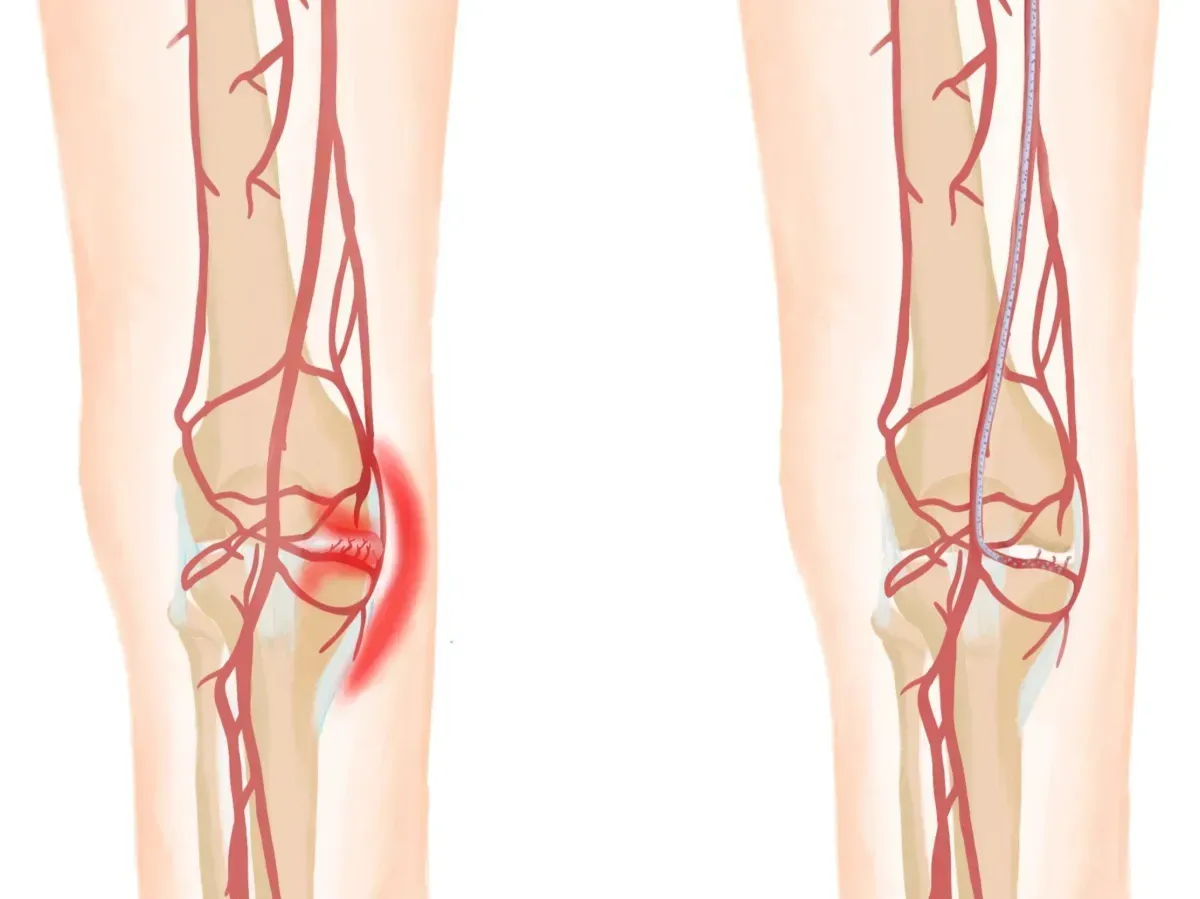

for moderate-to-severe bone-on-bone arthritis

GAE Eliminates Bone-on-Bone Arthritis with Just One, 20-Minute Procedure

Benefits of GAE

It's minimally invasive - no cuts or stitches needed.